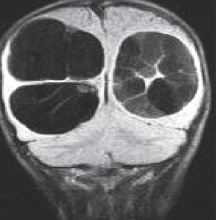

Кисты средней линии - киста прозрачной перегородки (cavum septi pellucidi), полость Верге (cavum Vergae) и киста промежуточного паруса (cavum veli interpositi) - являются нормальными структурами головного мозга плода. В течение 6 месяцев после рождения у большинства людей они запустевают, но могут и сохраниться. По-видимому, эти полости не имеют клинического значения и относятся к случайным находкам при МРТ головного мозга . Киста прозрачной перегородки (еще называют V желудочком) является медиальной стенкой боковых желудочков и ограничена спереди коленом мозолистого тела, сверху мозолистым телом и сзади столбами свода. Полость Верге представляет собой продолжение кисты прозрачной перегородки кзади и расположена между телами желудочков (рис.105). Обычно обе кисты сочетаются. Киста промежуточного паруса расположена в крыше III желудочка (tela choroidea), между треугольниками боковых желудочков на уровне отверстий Монро. Она ограничена сверху мозолистым телом, cзади цистерной четверохолмия и снизу III желудочком.